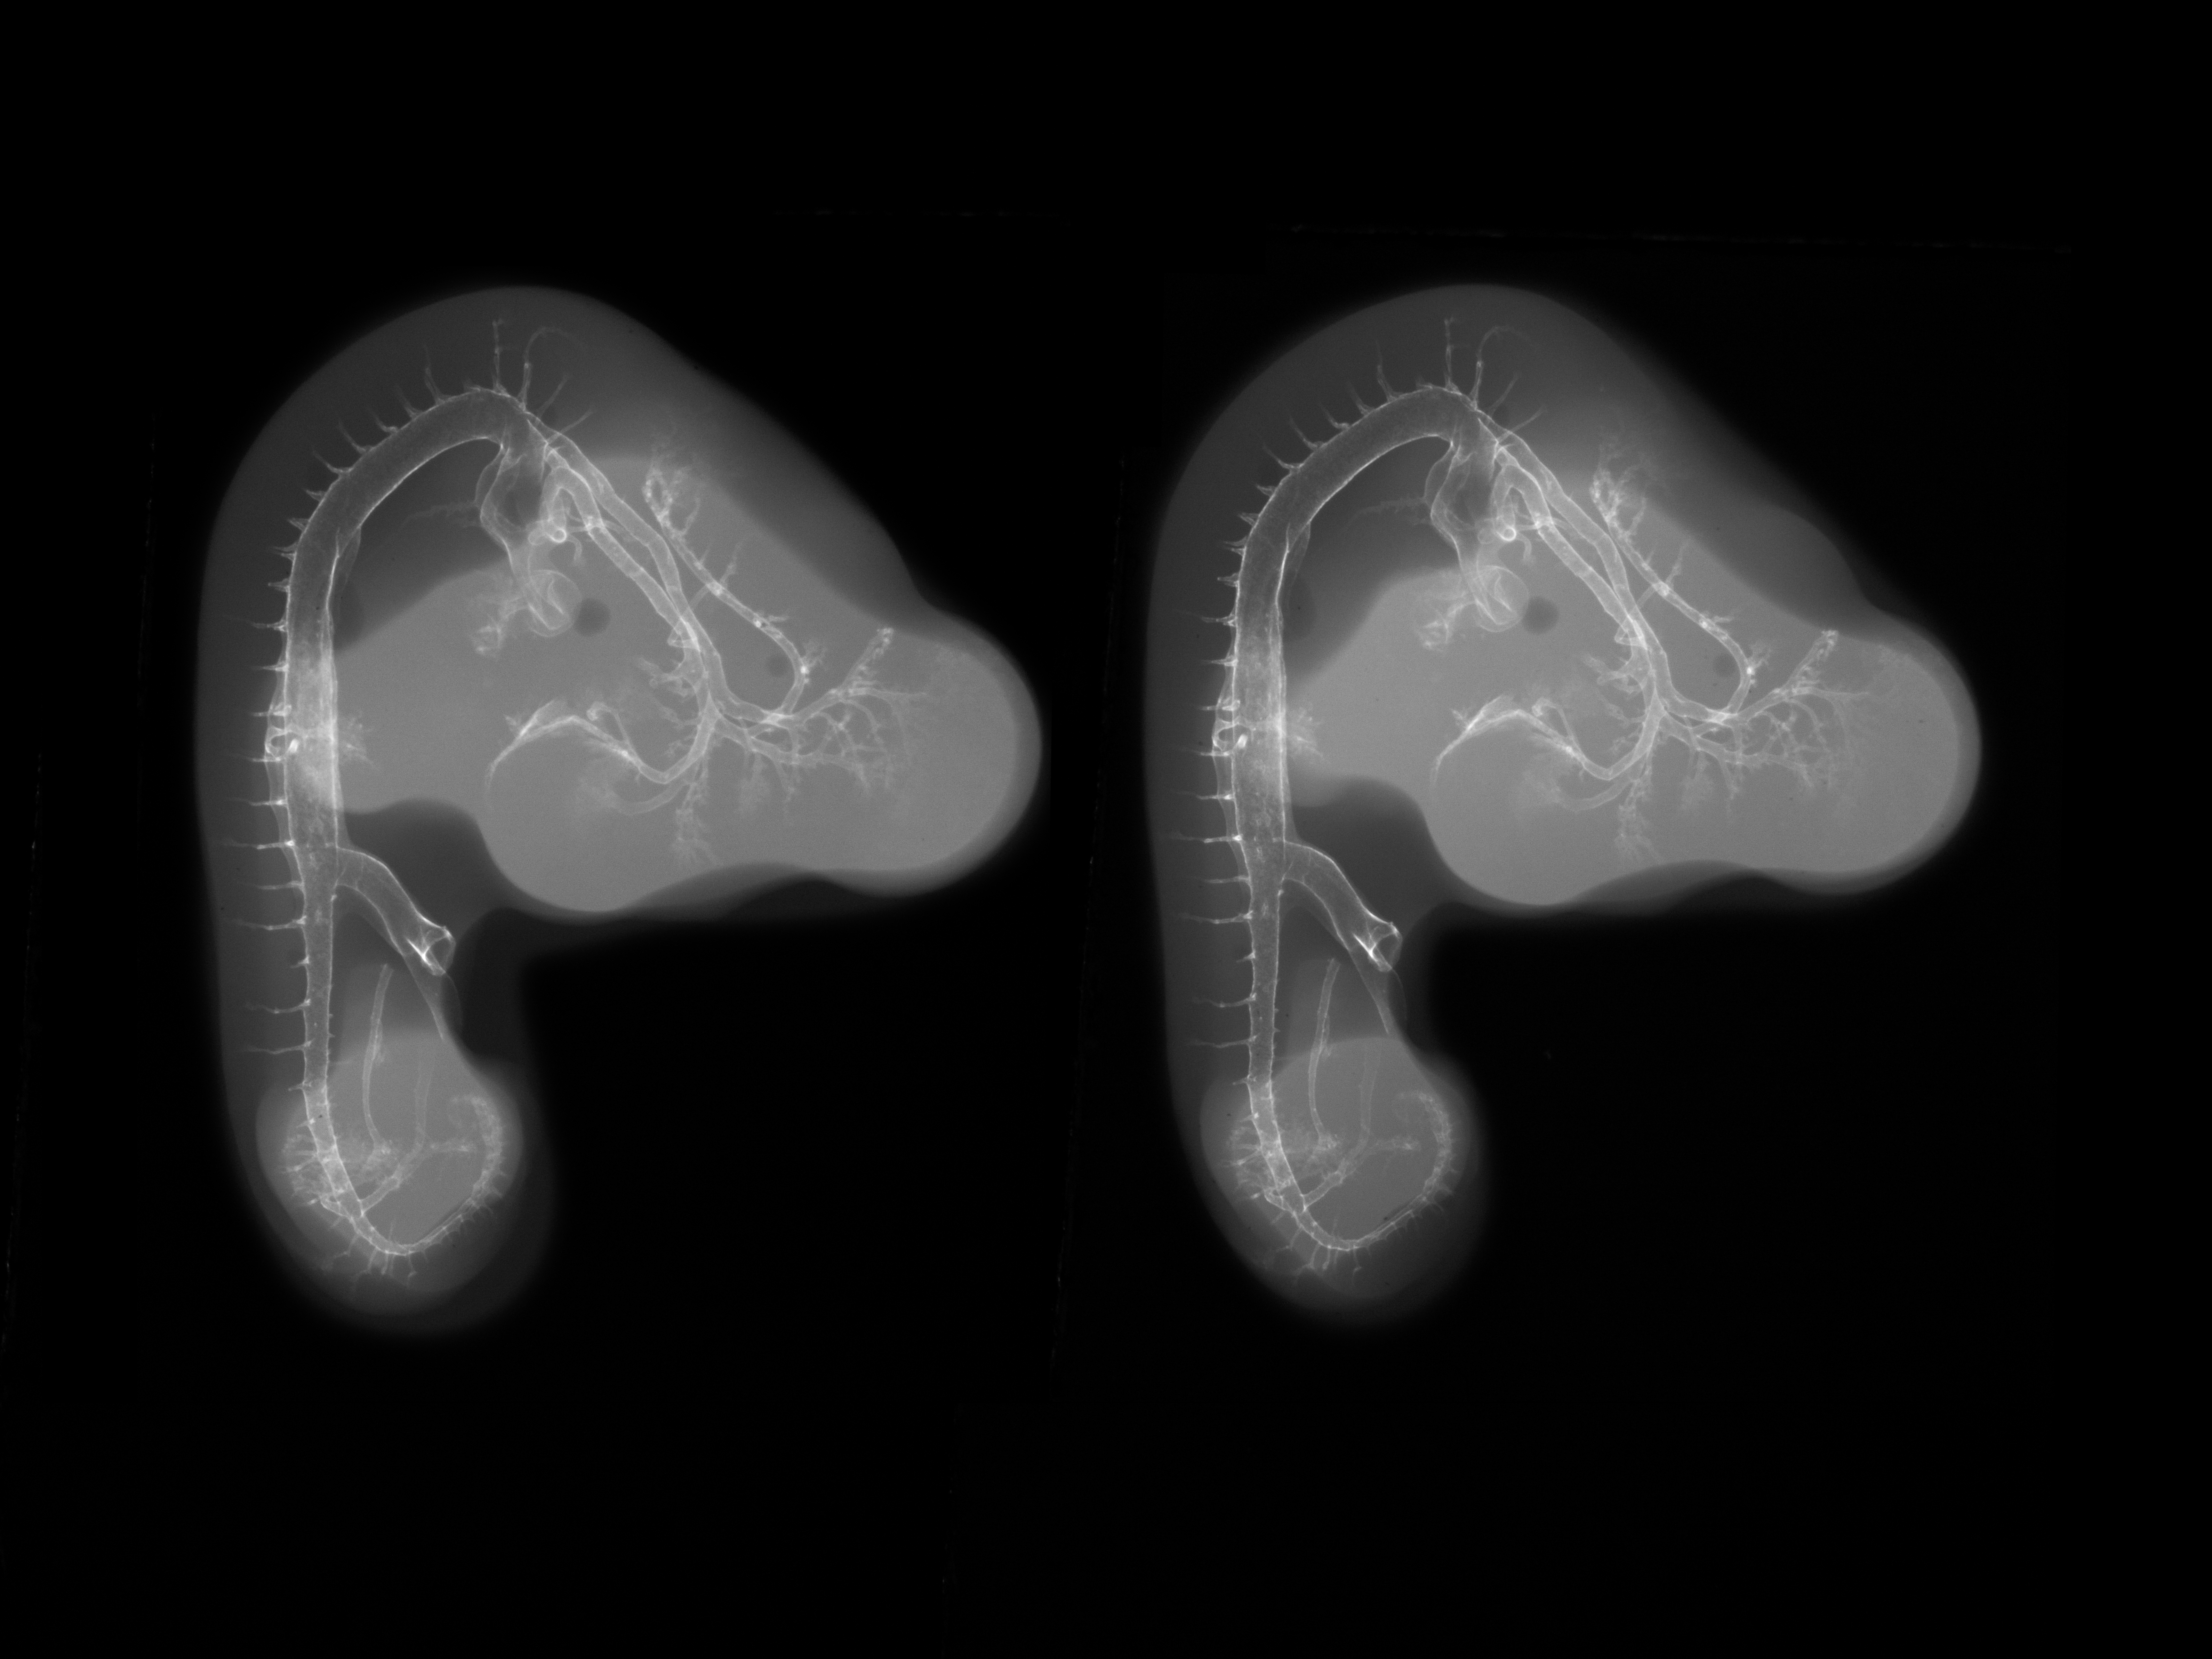

Chick Embryo Microangiography

Hamburger-Hamilton (HH) Stage 24 (approx. 4 - 4.5 days)

Stereo X-Ray Micrographs